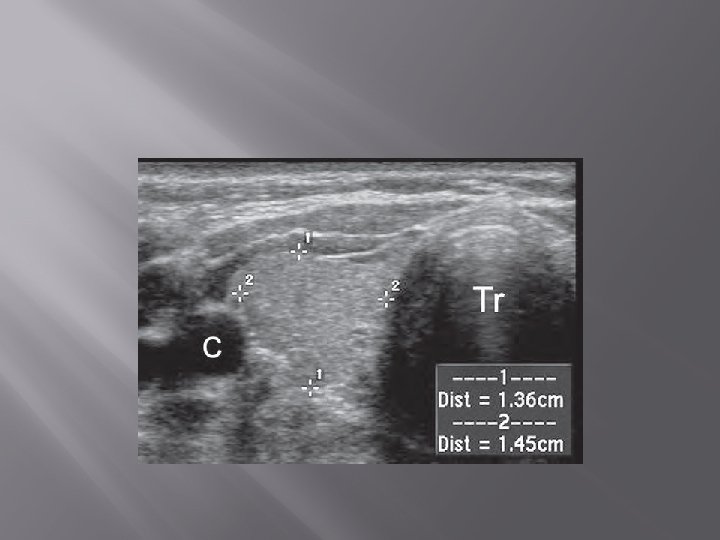

1. Ultrasonography (USG) � � Gray scale, color Doppler Transducer : linear frekuensi tinggi (7. 5 -15. 0 MHz)

� � Ukuran normal kelenjar thyroid orang dewasa Indonesia : 4 -4, 8 cm x 1, 0 -1, 8 cm x 0, 8 -1, 6 cm. Berat normal : neonatus 2 -3 gram. Orang dewasa 18 -20 gram

� Normal thyroid parenchyma has a homogeneous, medium-level to high-level echogenicity that makes detection of focal cystic or hypoechoic thyroid lesions relatively easy in most cases.